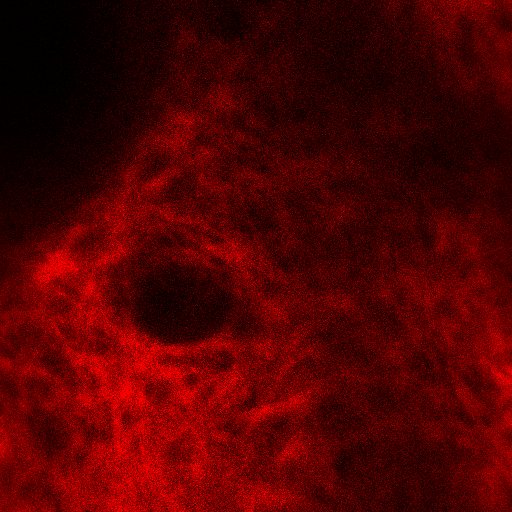

- 胶原纤维成像:SHG通道可直观显示胶原纤维的密度和排列变化,评估抗皱产品的功效。

图10. SHG通道胶原纤维—平面图像

图11. SHG通道胶原纤维—立体图像

注:

- 胶原纤维属于功能性蛋白质,较粗大,直径1~20μm成束状分布,排列紧密,并交织成网状。

- 双光子胶原纤维的扫描可观察深度一般为40μm,甚至更深。

- 可以在二次谐波通道观察到胶原纤维(红色),平面图像主要特征为纹理结构,呈现条带状或网状,立体图像由于不同深度的胶原纤维叠加,主要呈现为立体网状或蓬松的云状结构。